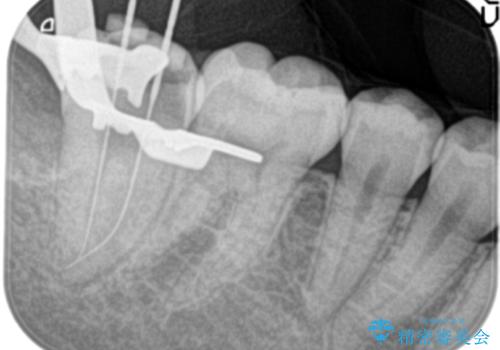

- 3日前からズキズキ痛み、冷たいものや熱いもので持続痛もあるとのこと。

不可逆性歯髄炎の診断で抜髄処置を行なっています。

根管治療は1回ごとにまとまった時間で治療を行うことにより2~3回の治療で完了します。

治癒不良の場合は外科的歯内療法の適応となります。